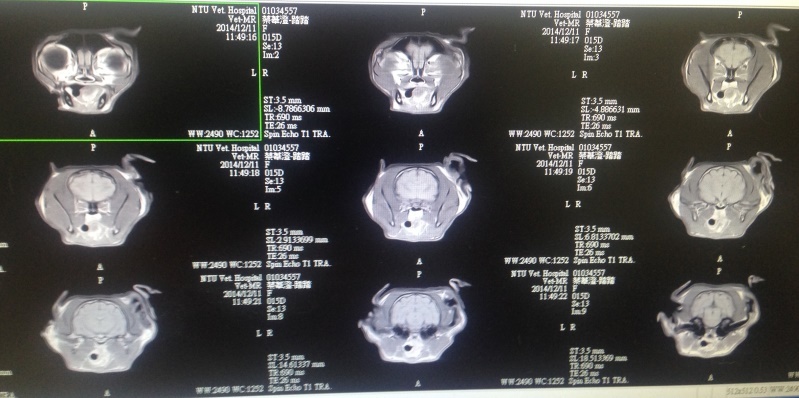

12/11踏踏安排做核磁共振以及腦脊髓液採樣分析,發現病無先天上結構異常,目前也沒有後天的腦部病變,血檢排除離子不平衡、中毒等狀況,醫師研判應該是不明原因自發性癲癇,有可能是遺傳基因的病變,有些在中年後腦細胞衰快速衰退,到時後腦部磁振造影才可能看出明顯的差異,目前腦狀況正常,海馬體也沒有萎縮,接下來就是需持續用藥物控制、追蹤,很慶幸至少在這些日子中,踏踏得到極好的控制沒有發病過,現在也確定並不是腦腫瘤病變,也代表踏踏只要按時服藥現階段與正常貓無異,還有很多幸福快樂的日子,還請各為幫忙踏踏檢驗的費用。

103.12.11 踏踏核磁共振以及腦脊髓液採樣分析血檢費用21610